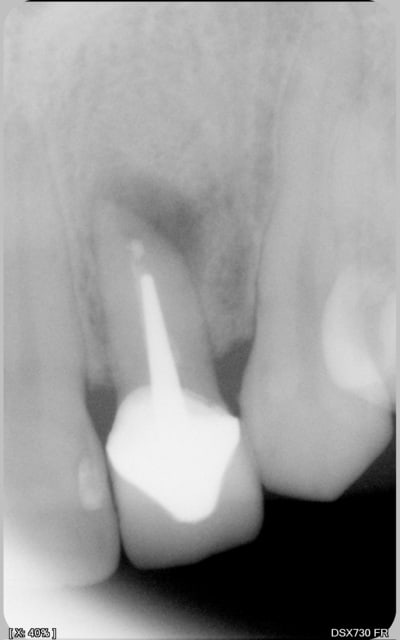

27/10/2012 à 02h21

alapex écrivait:

----------------

> Et l'endo ça marche , ou bien ?

j'aurais bien envie de répondre par une phrase de mon idole de jeunesse Garcimore.

plus sérieusement, ta question est légitime car la rétroalvéolaire que je voulais joindre n'est pas passée (format TIFF) et je m'en aperçois que maintenant.

Je pense que là c'était mort!